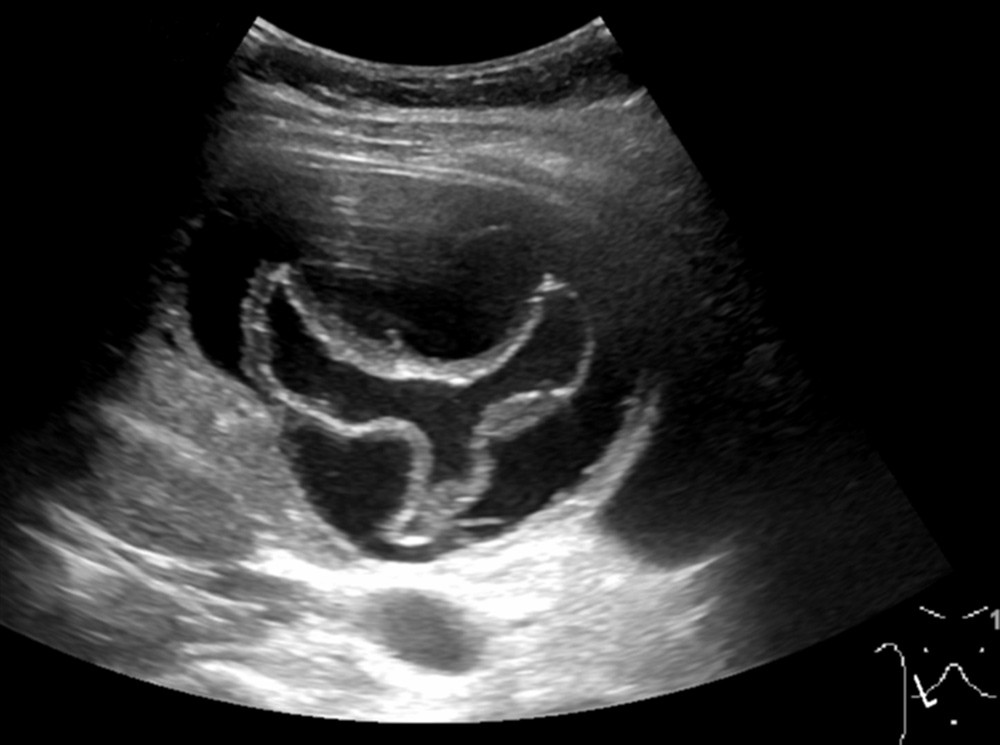

Ultralydundersøkelsen viste en cyste i leveren. Største diameter var 10 cm. Den hadde en foldet indre struktur, forenlig med en separat, flytende indre membran, såkalt vannliljetegn. Dette funnet er karakteristisk for ekinokokkcyste. Pasienten ble henvist videre til infeksjonsmedisiner. Serologiske prøver var også positive for ekinokokker.